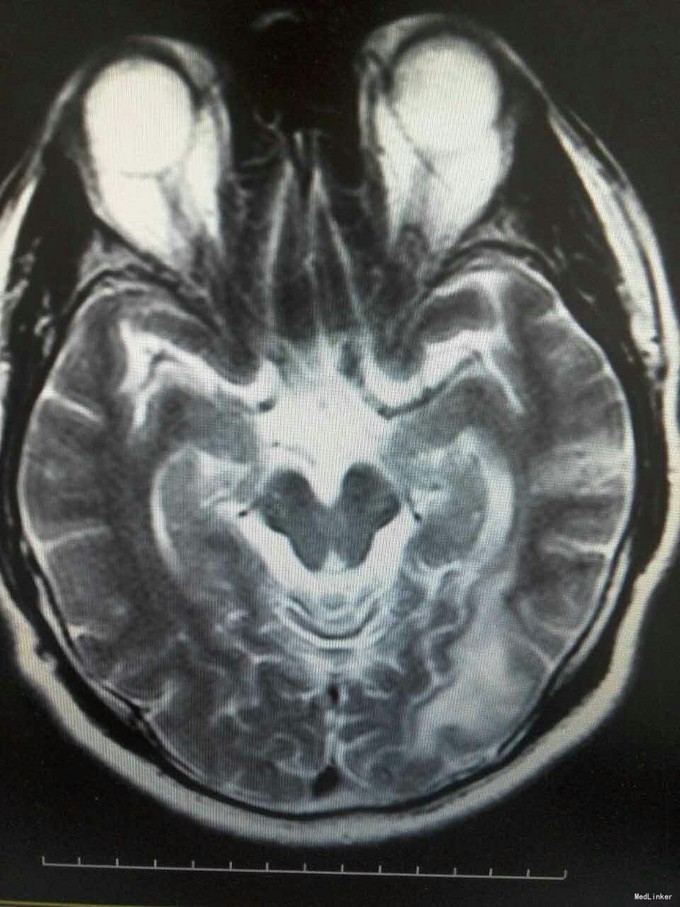

患者姜磊,男,49岁,主因"发作性视野缺损、失认8年余"于2015-11-20再次入我院,患者缘于8年前无诱因出现发作性视野缺损,伴阅读能力、理解力、认知能力下降,每次发作症状持续约3-5分钟左右,可自行缓解,无意识丧失、视物旋转、言语不利,无肢体活动障碍、大小便失禁。入院复查头颅MRI平扫+增强示:原左侧小脑幕、颞叶炎症治疗后,与2014-09-10日片比,病灶较前增多、增大。8年来间断在我院以:颅内非特异性炎症、症状性癫痫、高血压病 住院治疗,患者症状时轻时重,病灶反反复复,激素治疗有效。 病史汇报: 于2007年12月12日因"发作性视野缺损、失认1月"入我院,查头颅MRI示:左侧幕上颞底片状异常信号,并局部强化,考虑:炎症可能,肿瘤不排除;行腰穿检查,颅压120mmH2O ,外观清亮,脑脊液常规、生化均正常。脑电图轻度异常。给予复方磺胺甲恶唑片、青霉素、阿昔洛韦、激素(醋酸泼尼松片)等治疗。 2008年1月8日复查头颅MRI示:原左侧幕上颞底炎性病变范围缩小,综合考虑原颅内病变为炎性病变。于2008年1月19日出院,共住院37天。出院后仍间断出现发作性视野缺损症状。于2008-5-6复查头颅MRI示原左颞叶病变范围有缩小,支持局灶性脑炎的诊断。于2008.5.22~6.12予青霉素480万单位2/日巩固治疗30天。鉴于反复出现发作性视野缺损症状,于2008.6.5诊断性服用卡马西平片后上述症状未再发作,于是坚持服用卡马西平片(0.1g3/日)1年,服药期间未再出现发作性视野缺损症状。 于2012-05-29再次因"发作性双眼右侧视野缺失、闪烁感6天"入院,查头颅MRI示:原左侧幕上颞叶病变治疗后改变,考虑为炎性病变,结核可能。行腰穿示压力125mmH2O,脑脊液常规:颜色:无色,透明度:水样透明,潘氏试验:阴性,红细胞计数:80×106/L,白细胞计数:0x106/L,单个核细胞75%,多核细胞20%,脑脊液生化:蛋白508mg/L,葡萄糖3.3mmol/L,氯化物115.4mmol/L。脑电图印象:基本节律为低-中幅的α波, 频率调幅调节欠佳,分布可,左侧枕区波幅可见较右侧枕区减低。头前区可见少量低幅θ波及β波。深呼吸中见4-5hz慢波增多,有时呈短至中程节律,头前区为著,左侧偏胜。深呼吸后恢复好。睁闭眼试验:半抑制。闪光刺激:未见异常。脑电地形图:以α功率为主,可见θ功率。结论:轻度弥慢性异常脑电图及地形图;给予改善循环、营养神经、活血化瘀、脱水、激素等对症治疗。住院期间未再出现上述发作。 于2013-1-5再次因"发作性双眼右侧视野缺失、闪烁感1周。"入院,行头颅MRI示:左侧颞叶病变治疗后改变,与2012-07-24日片比,左侧小脑幕病变较前增大,左侧颞叶出现新病灶。给予改善循环、营养神经、活血化瘀、抗癫痫、抗感染(青霉素)、激素冲击(甲强龙)治疗后病情好转,于2013-4-15复查头颅MRI病灶再次缩小。患者出院后上述症状仍偶有发作。 于2014-5-12、2014-9-10复查头颅MRI病灶有增大趋势,再次给予抗炎(激素)等对症治疗后,于2014-11-24再次复查头颅MRI示:原左侧小脑幕、颞叶病变治疗后改变,与2014-09-10日片比较,较前明显缩小,水肿较前明显减轻。